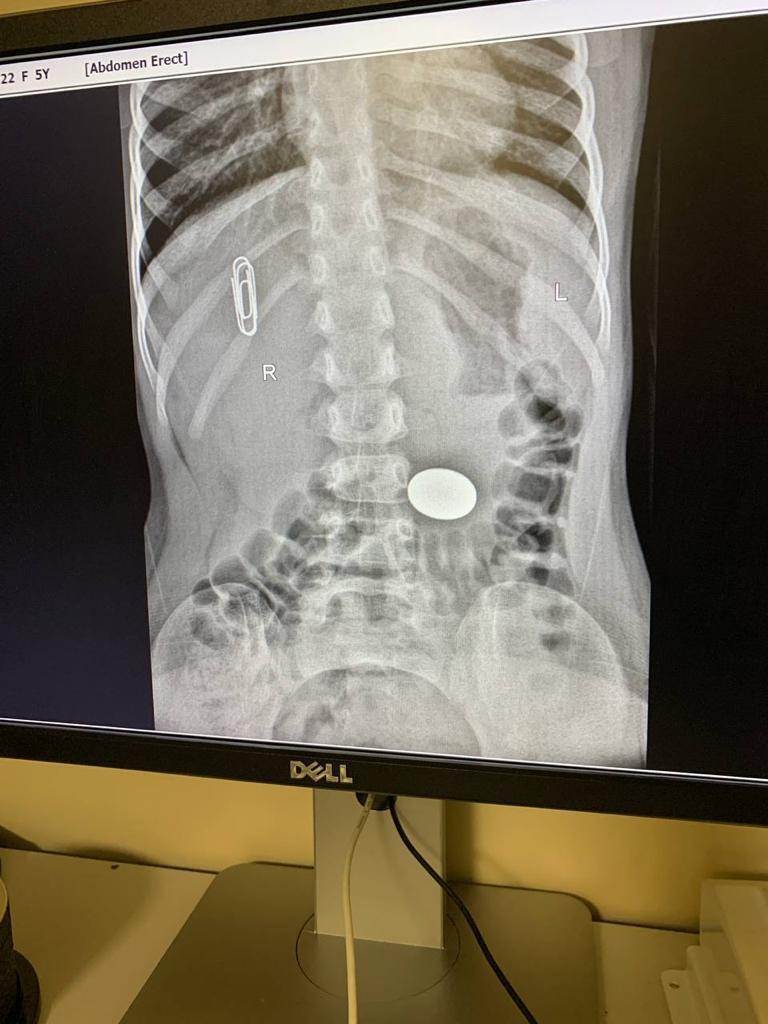

Через 20 минут после операции, в приемное отделение залетают ошарашеные родители с чадом около 4-5 лет. Монету проглотила.

Делаем Рентген

*скрепка не внутри, она для ориентации*

Я хмуро посмотрел на рентгенолога. Рентгенолог посмотрел на снимки, а потом на меня (искра, буря, безумие) - В поперечно-ободочной. Сама выйдет. - заключил он.

Посмотрели. 5ти Рублевая монета в желудке. Достали без происшествий. Отпустили с богом.